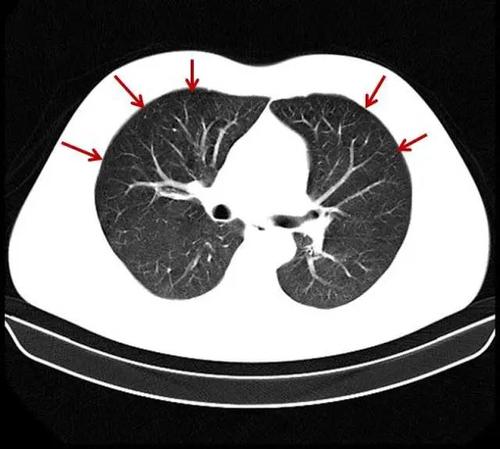

ct经典图谱:肺气肿ct典型图谱,一学就会

肺气肿的影像诊断

轻度肺气肿ct影像